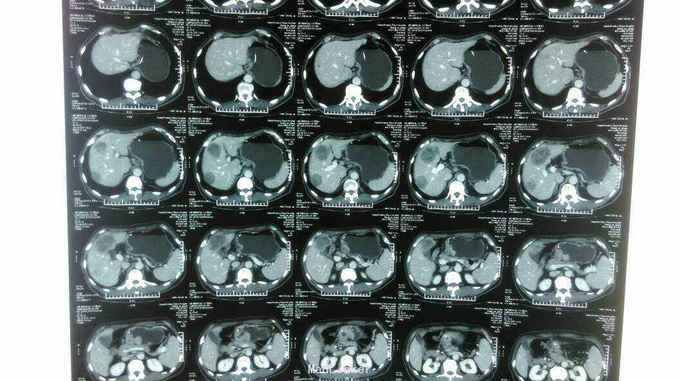

患者:男,62岁,主 诉:残胃癌多发转移化疗后,恶心呕吐5月余。 现病史:患者于2014年9月份自觉进食后上腹部饱胀感,就诊于忻州市人民医院,胃镜提示:胃大部切除术后,吻合口大弯侧粘膜隆起,充血,水肿,伴糜烂,质 脆,易出血,于2014年9月23日就诊于中国医学科学院肿瘤医院,诊断残胃癌,中分化腺癌,全腹部示CT提示:胃远端呈术后改变,吻合口扩张不良,吻合口壁厚,吻合口周围、胃左区新发现多发不均匀结节,大者短径约1.6cm;腹腔肠系膜根部、腹膜后多个小淋巴结;肝脏新出现多发结节,大者直径约1.5cm,考虑转移,盆腔少量积液。于2014年11月15日行XELOX方案化疗一周期,具体用药:奥沙利铂150mg,d1希罗达1500mg早 2000mg晚d1-d10,14天重复一次。后于忻州市人民医院2014年11月至2015年01月给予XELOX 方案化疗全身化疗5周期,化疗第二周期后,患者上腹部饱胀感减轻。于2015年3月12日就诊山西省肿瘤医院,全腹部CT提示胃腔缩小,残胃壁增厚,最后处约1.9cm,,残胃下方系膜内一枚囊性结节,大小约2.9X2.3cm,转移不除外:肝脏S8段一枚低密度灶,大小约为0.6X0.4cm;右肺中叶结节,大小约为1.6X1.4cm,肝脏S8段动脉期环形强化结节,考虑转移,右肺中叶炎性病变,继续给予行XELOX方案化疗2周期(奥沙利铂200mg,卡培他滨1.5g/次,2次/日,共14天)。因骨髓抑制明显,于2015年5月4日入该院后给予卡培他滨化疗一周期(卡培他滨2g/次,2次/日,共计14天)。2015年6月10日入该院复查CT提示肝内多发低密度影,部分新增,右肺中叶局限性肺不张,纵膈内多发小淋巴结,给予更换TP方案化疗一周期(多西他赛120mg,顺铂90mg),治疗结束于6月25日出院。出院后患者间断出现恶心、呕吐,于7月13日入该院复查胸腹部CT:残胃壁局部略变薄;头颅核磁未见异常。患者体质较差,不能耐受化疗,于7月21日始口服阿帕替尼250mg/日治疗。后患者间断出现恶心、呕吐,呕吐物为胃内容物,8月底患者停服阿帕替尼。9月8日入该院复查提示:肝脏多大转移增大,患者恶心、呕吐明显,予以留置鼻饲营养管,行EOF化疗一周期,共计用药:奥沙利铂150mg,表柔比星50mg,氟尿嘧啶3.0g,化疗所致骨髓抑制Ⅱ度。2015-11-02再次入住山西省肿瘤医院给予康莱特静点等对症治疗9天。目前患者每日鼻饲饮食后呕吐7-8次,每次呕吐量约40-50ml左右,全身疲软,精神食欲差,睡眠尚可,大便3-4日一次,较干结,小便基本正常,近3月体重下降约5kg。 既往史:既往患者高血压病史15年余,最高血压达180/100mmHg,平素口服尼福达片1片/日降压治疗,血压控制尚可;2型糖尿病10年余,曾皮下注射诺和灵30R控制血糖,近1月因进食量减少,已停用胰岛素治疗;40年前因“十二指肠穿孔”行胃大部除术;5年前山西医科大学第二医院确诊右半结肠癌行右半结肠切除术;10年前曾行阑尾切除术

诊断: 中医诊断: 胃癌 痰气交阻 西医诊断:残胃癌 中分化腺癌 浸润型 Lauren分型:肠型 肝转移 胃周 腹腔淋巴结转移 多疗程化疗后 空肠营养管植入术后: 呕吐原因待查 中度贫血 右半结肠癌(术后、化疗后) 2型糖尿病 治疗:入院给予查腹部立位片未见液气平面,给予止吐,输血纠正贫血,营养支持,中医中药扶助正气治疗,行动脉介入化疗药灌注(奥沙利铂150mg+氟尿密啶0.75g),肝转移灶(吡柔比星20mg+碘化油6ml)栓塞治疗。